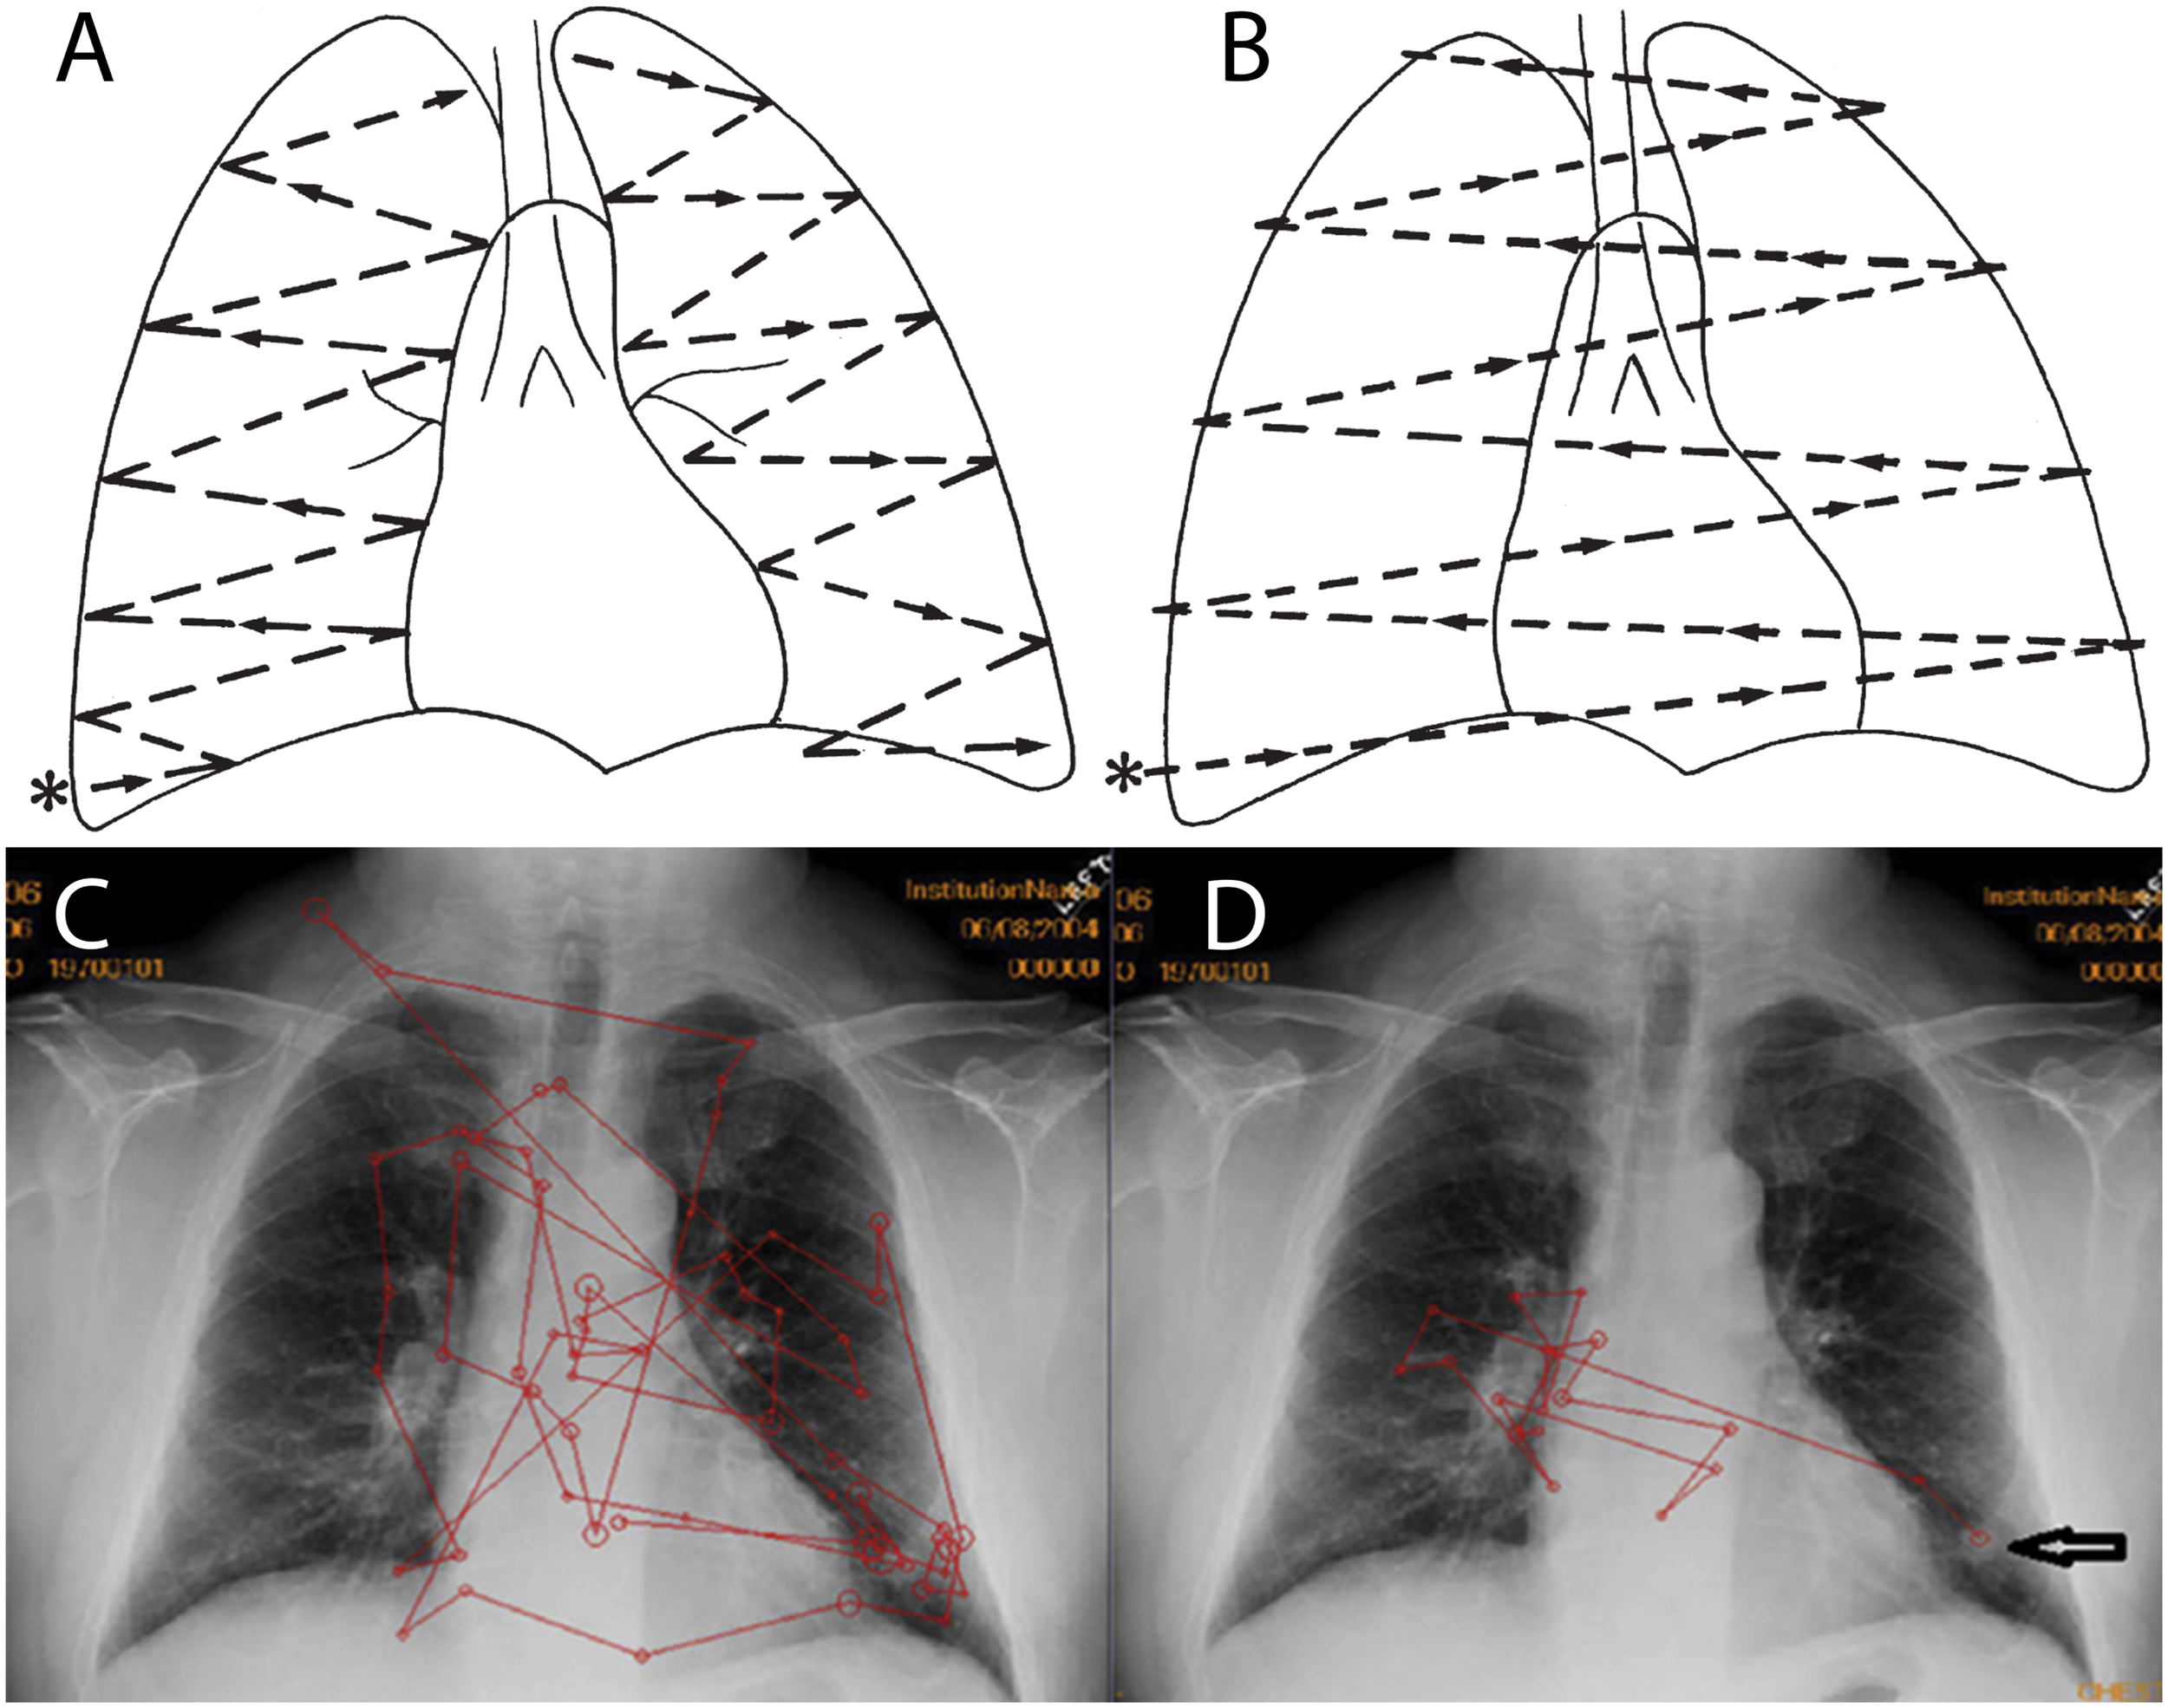

FIGURE 1

Reprinted from Goodman and Felson (2007) with permission. (A,B) Proposed lung search pattern. (A) This commonly taught search pattern for examination of the lungs during chest radiograph (CXR) interpretation involves starting at the right base (∗) (the costophrenic angle) and examining the right and then left lungs. (B) A second look is then performed in order to compare the right and left lungs as bilateral symmetry is assumed to be useful in recognizing abnormalities (Carmody et al., 1984). Reprinted from Waite et al. (2017a) with permission. Typical scanpaths of a novice (C) and an expert (D) radiologist, both searching a CXR which has a nodule at the left base (arrow in D). This free search pattern (D) is typically employed by experts and differs from the formal radiologic training given in residency. Instead, it indicates the flexible use of search strategies as a function of immediate visual information. The expert radiologist (D) has more efficient scanpaths (red lines) than the novice (C), with fewer fixations (circles), less coverage of the image, fewer saccades, and faster arrival at the abnormality.

Because novices lack the ability to generate a rapid and accurate global impression of an image, they may benefit from an orderly and comprehensive search pattern/order (Goodman and Felson, 2007; Auffermann et al., 2016) (Figure 1). If readers adhere to a specific order or search pattern in the inspection of anatomical structures, they may achieve more complete coverage of the image, reducing the number of overlooked abnormalities. Although full coverage could also be achieved by inspecting anatomical structures in a random order, keeping a specific order of inspection provides readers with a mental checklist (Kok et al., 2015). Thus, one commonly taught technique, “systematic viewing,” is to inspect anatomical areas in a fixed order.

Expert Search Patterns

One potential reason that pre-defined search patterns fail to consistently improve resident accuracy is that experts themselves do not read plain films in a consistent, standardized manner. Therefore, the various advocated search methods are not consistently used in practice (Kundel and La Follette, 1972) (Figure 1). Instead, experts use a variety of non-systematic search patterns, so-called ‘free search,’ when looking at images (Auffermann et al., 2016). An evolution of search patterns from medical students to attending radiologists was noted in one study but attending search patterns were not systematic; eye movements were more affected by the findings on the radiograph than any preplanned search pattern (Kundel and La Follette, 1972). A pioneering study by Tuddenham and Calvert (1961) found a wide variation in search patterns among readers. Ironically, the only observer with a reproducible search pattern failed to report findings noted by observers with inconsistent patterns (Tuddenham and Calvert, 1961). These findings are remarkably consistent with those from studies conducted over 50 years later, suggesting that consistent search patterns do not help, and indeed might be detrimental, to accurate diagnosis (Kok et al., 2015). Carmody et al. (1984) also found that, although radiologists are taught to compare both lungs (to look for asymmetric findings), less than 4% of their eye movements indicated such comparison scans, further illustrating the gap between radiologic instruction and practice.